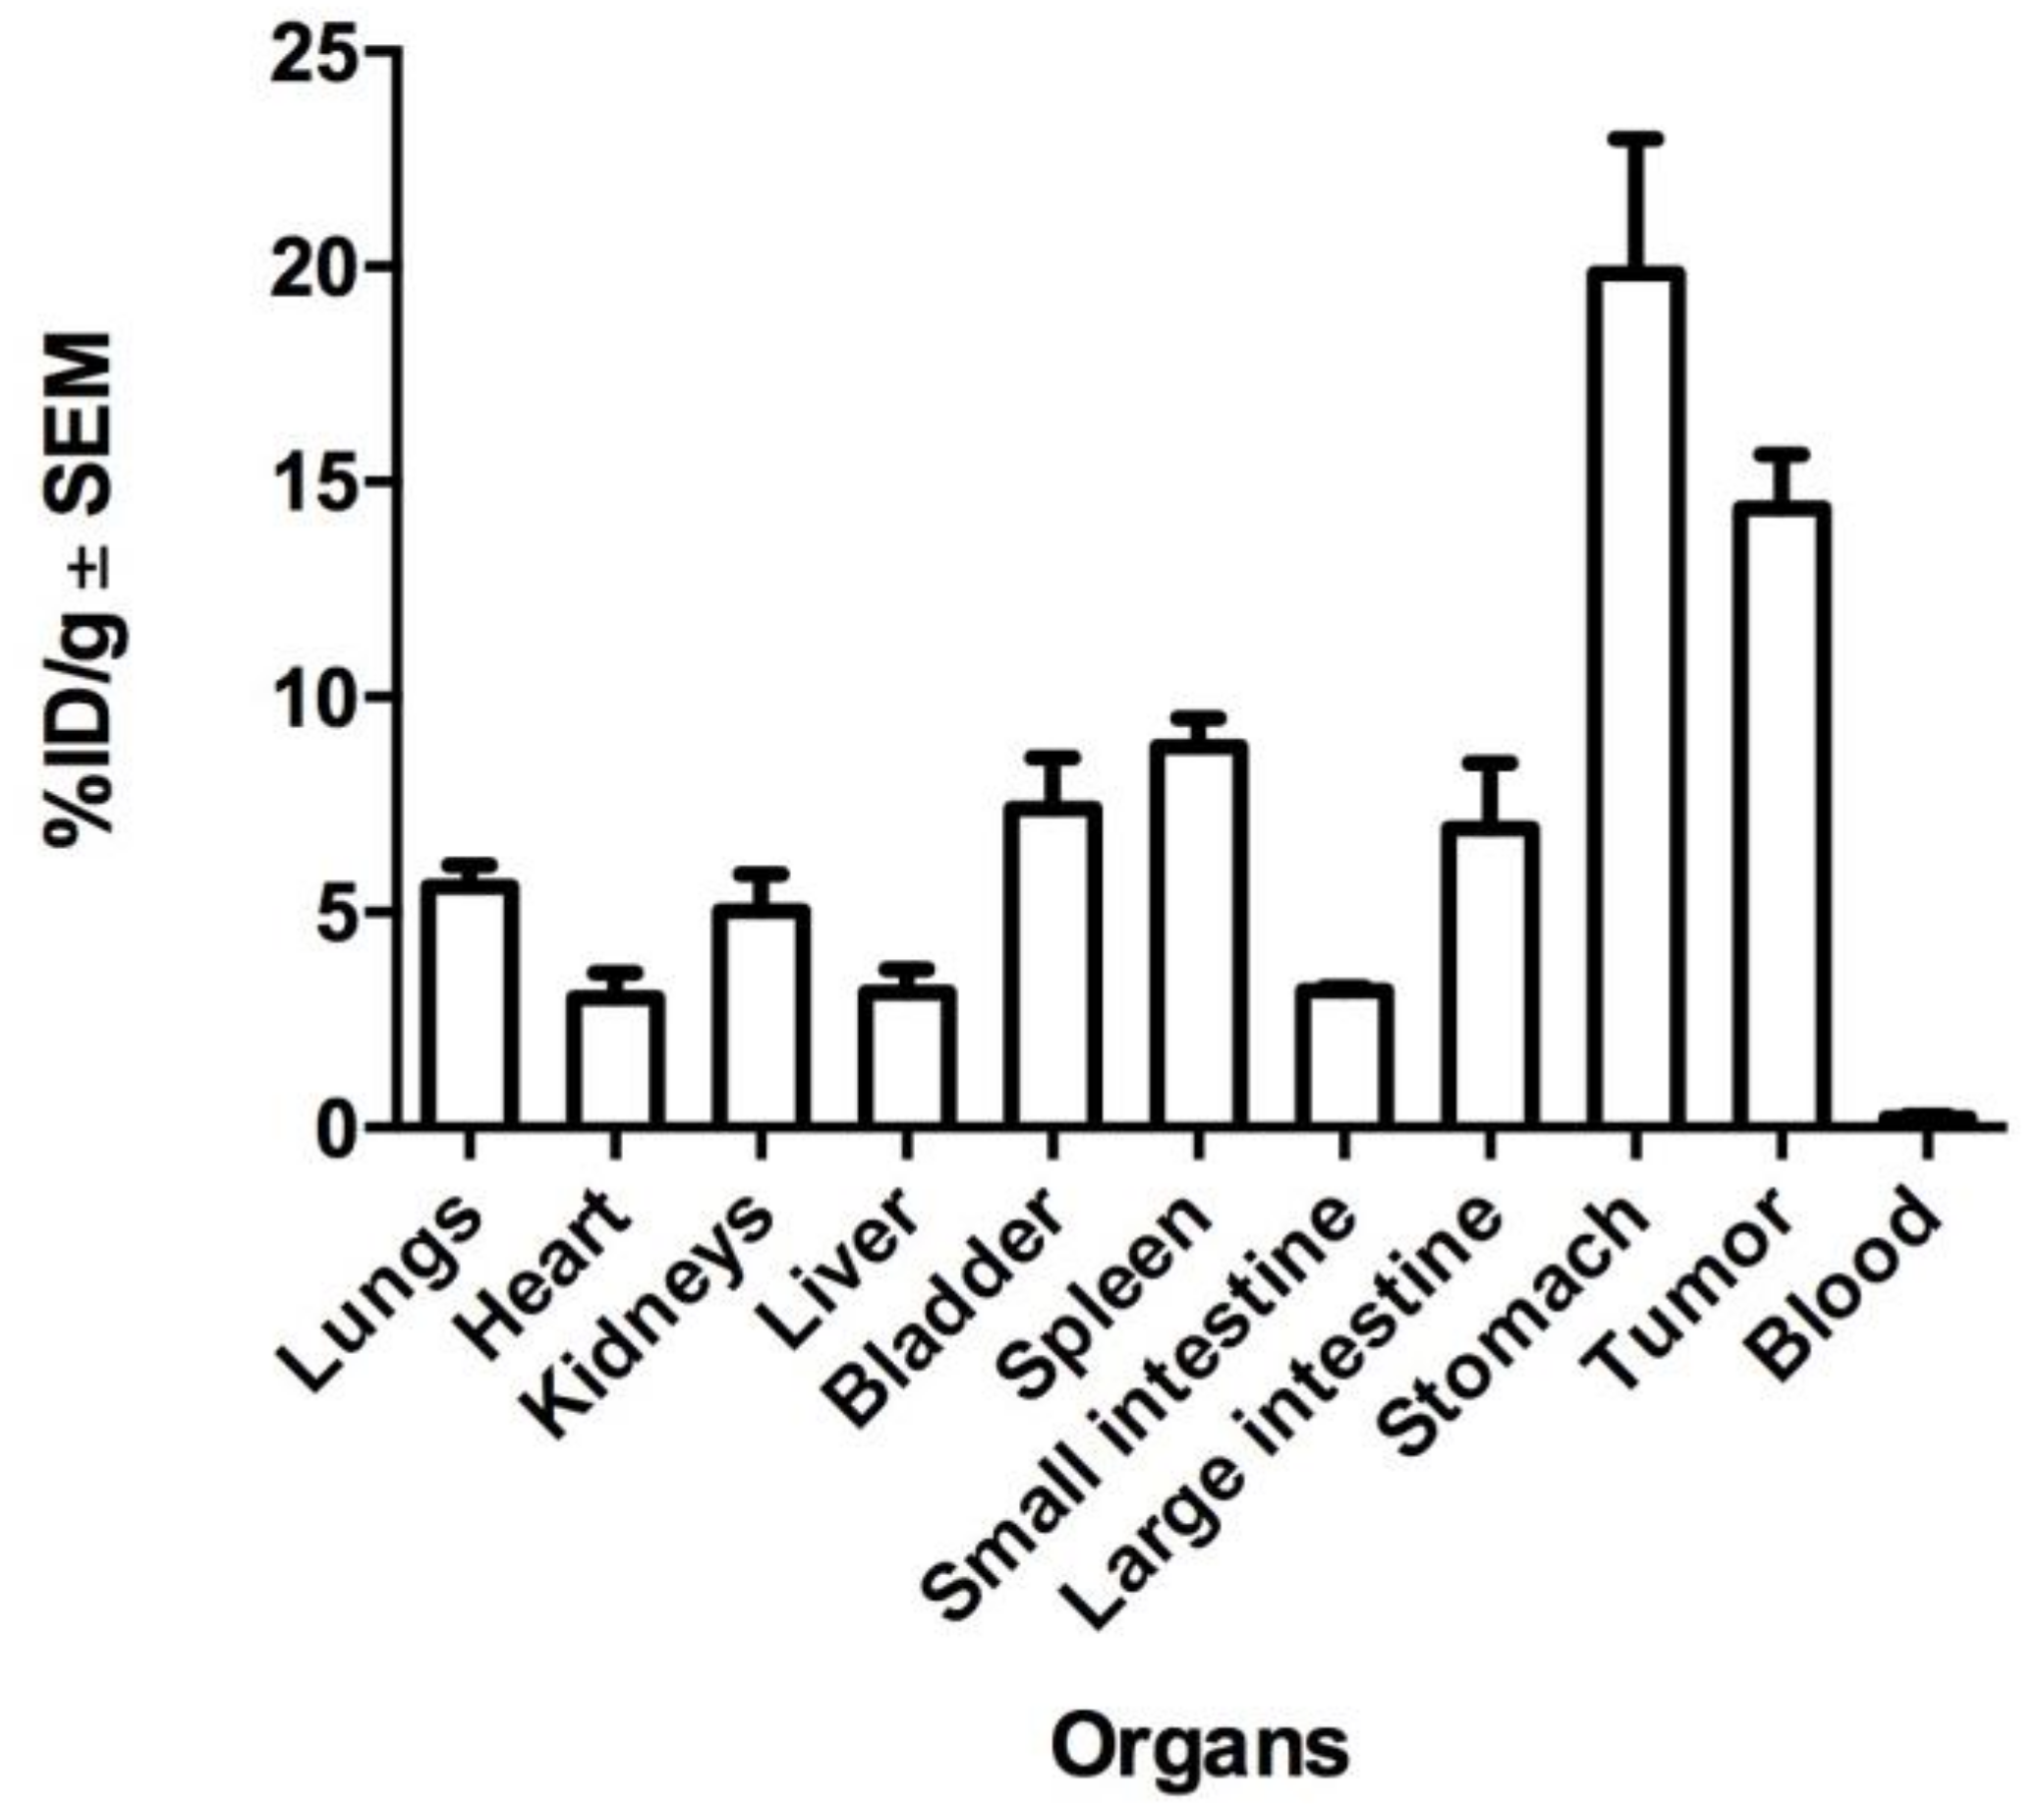

2.4. Biodistribution and Tumor Uptake in Mesothelioma Xenografts

4.8. Biodistribution and Molecular Imaging Studies